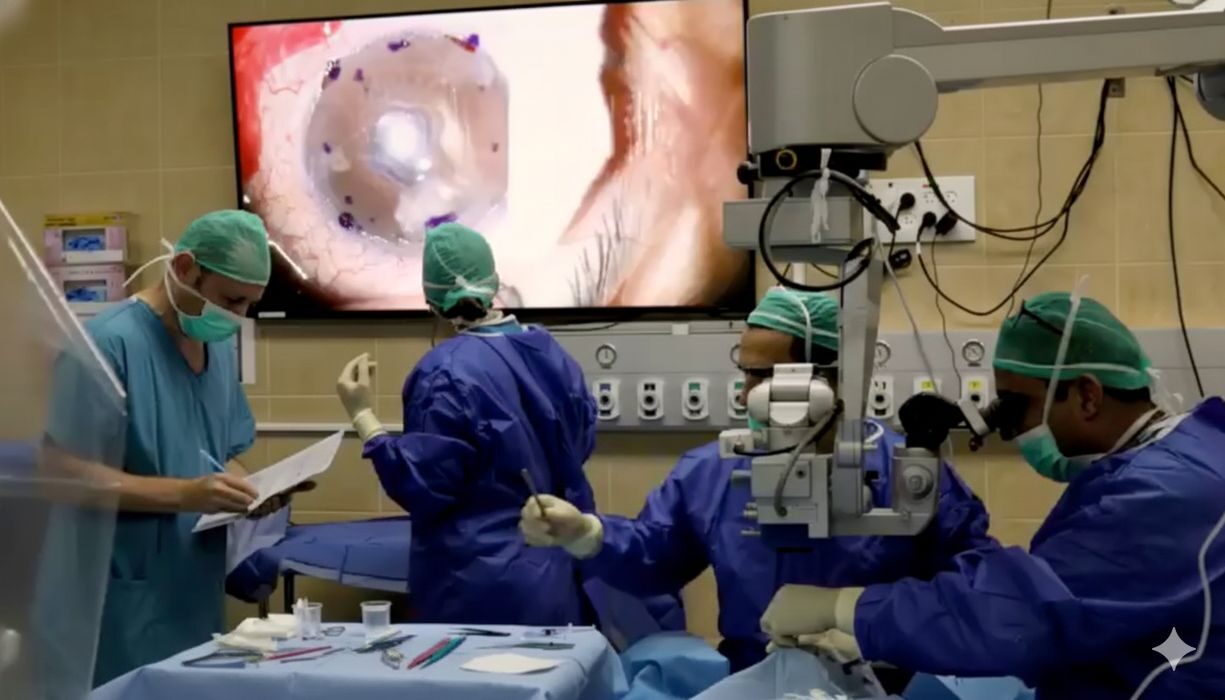

Precise Bio Reveals Scalable 3D Bioprinting Process After First Human Cell-Printed Cornea Transplant

A company has deployed a scalable process to 3D print human corneas.

KeratOprinter Project Aims to 3D Print Corneas to Address Global Donor Shortage

The KeratOPrinter hopes to solve corneal blindness with new technology.